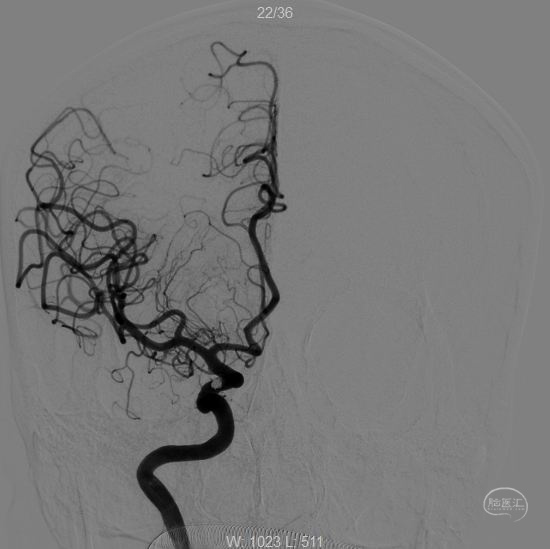

术后工作位造影

换角度观察,栓塞满意。

正位

术后第二天CT:未见异常,术后一周顺利出院。